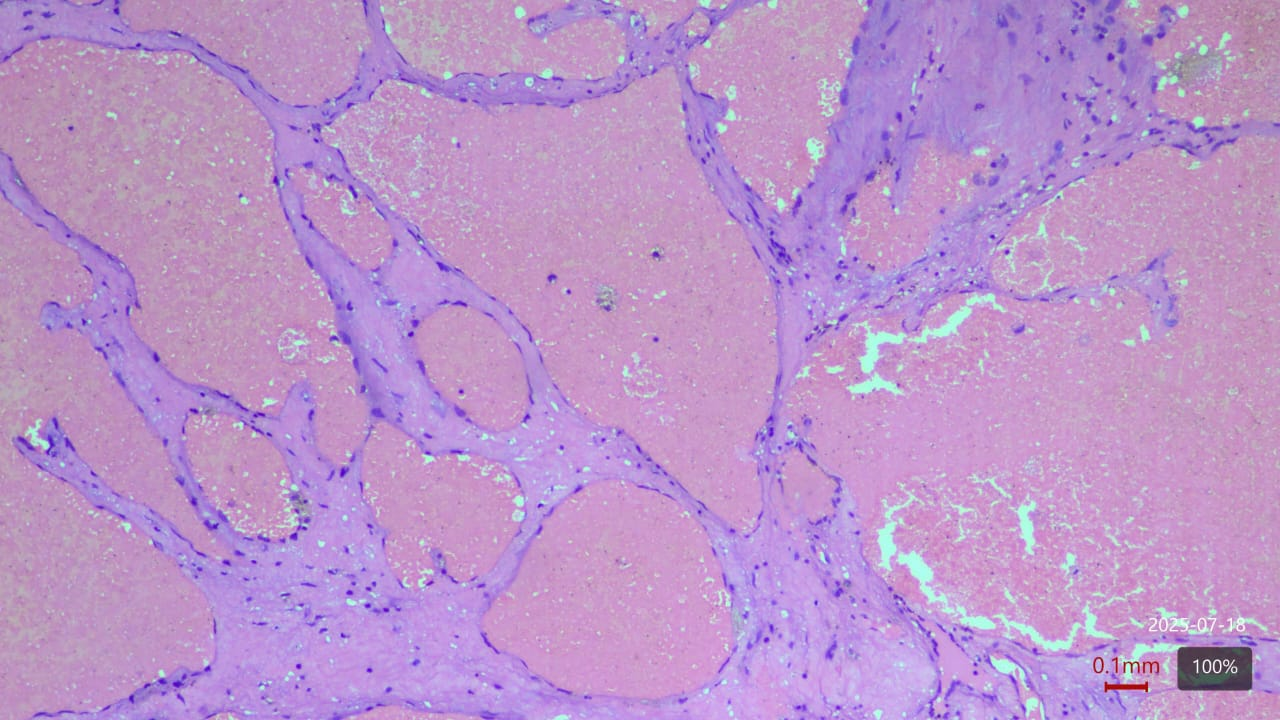

A young 23 year old female first presented in 2015 with complaints of right-sided chest pain and swelling. A thorough clinico-radiological evaluation was done and general surgeon consultation sought. Imaging revealed an expansile lytic lesion of the right 9th rib (Fig 1). Other long bone x-ray evaluation was done and found no abnormalities. We planned for excision biopsy of 9th rib and patient underwent surgical excision (Fig 2). Histopathological examination confirmed a benign intraosseous hemangioma(Fig 3). Post-operative recovery was uneventful. 6 monthly followed by yearly radiological follow-up was being done till pre-covid period. Patient lost to follow-up during 2020-2022 Covid-19 period.

In 2022, the patient presented with progressive pain and restricted range of motion of the right hip following minor trauma. She was re-evaluated clinically and imaging was done. Radiographs (Fig 4 ) and MRI (Fig 5) revealed an expansile lytic lesion of the right proximal femur consistent with intraosseous hemangioma. Due to risk of pathological fracture we planned for fixation of right proximal femur. She underwent right proximal femoral bone excision biopsy and dynamic hip screw fixation with iliac–fibular strut bone grafting (Fig 6). Post-operative period was uneventful. Started partial weight bearing after 45 days followed by full weight bearing by 90 days. Very good radiological incorporation of graft noted and fixation was stable radiologically (Fig 7). Histopathology report suggestive of benign bone hemangiomatous tissue without any features of malignancy (Fig 8).

Histopathology

Biopsies demonstrated benign vascular channels lined by flattened endothelial cells with no atypia or malignant transformation. Despite the benign appearance, radiological progression persisted (Fig 8).